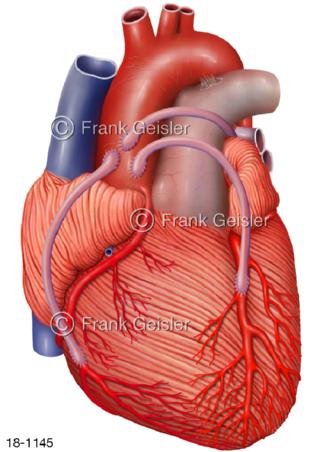

18-1145 Herzkranzgefäße Herz, Bypass nach OP